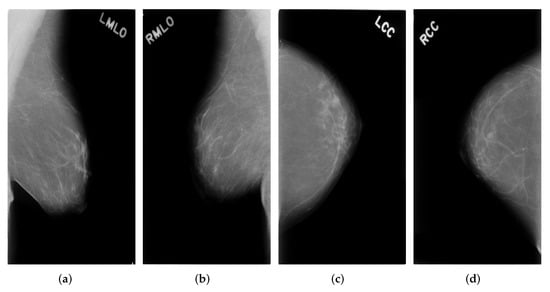

One breast usually has four mammograms including LMLO, RMLO, LCC, RCC. An example can be seen in Figure 1.

Figure 1. Four example mammograms of one breast (a) Left MLO view images (b) Right MLO view images (c) Left CC view images (d) Right CC view images.